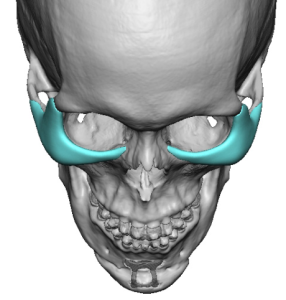

3D CT Findings in NOV

- Augment the infralateral orbital rim

- Improve the globe-to-rim relationship

- Provide structural support to the lower eyelid

- Reduce scleral show and tear trough depth

1. Infraorbital Rim Augmentation

- Saddles the infraorbital rim

- Adds both vertical height and horizontal projection

- Produces a superoanterior (3D) expansion of the rim

- Enhances lower eyelid support